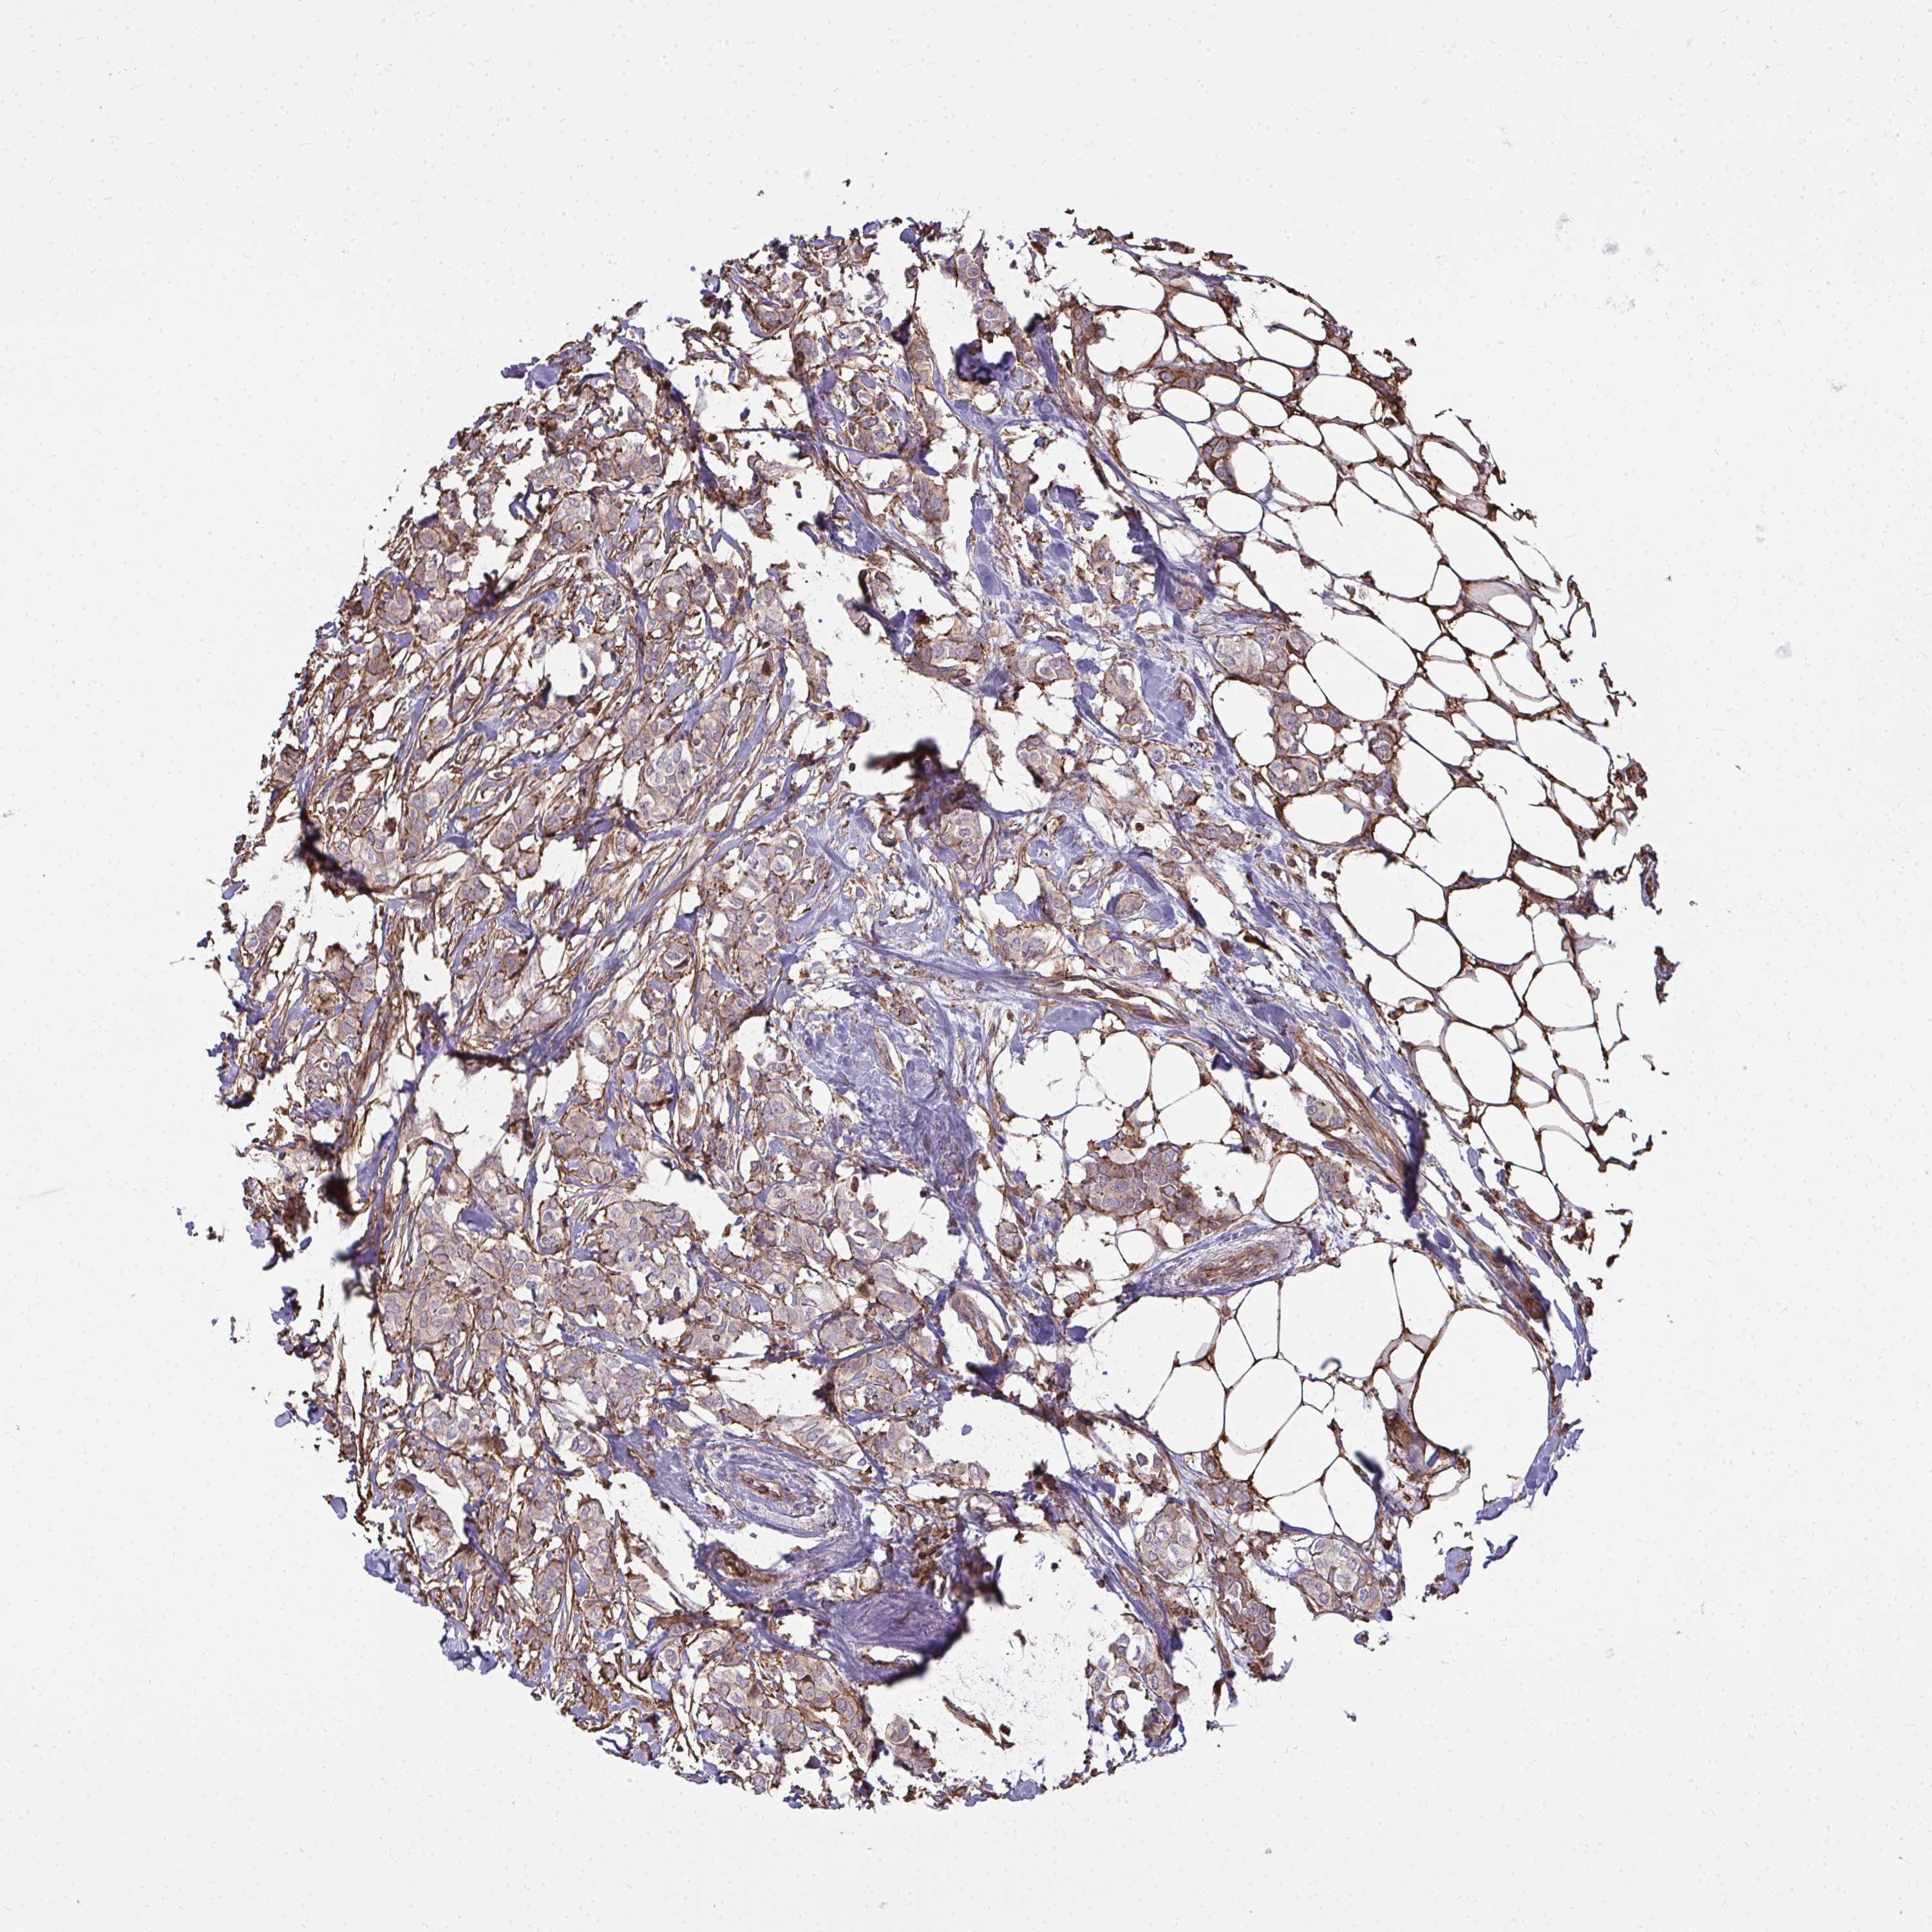

BRCA TCGA BRCA VALIDATION PROTEIN EXPRESSION

Breast cancer

Human cancer